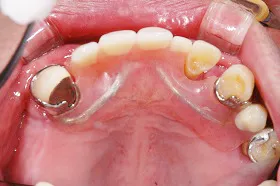

インプラントを使用した入れ歯の症例

■治療前

■治療後

| 主訴 | しっかりかみたい(咬合障害) |

| 治療方法 | 費用を抑える為、全てインプラントではなく、インプラントを土台とした入れ歯の治療 |

| 治療期間 | 約6か月 |

| 通院回数等 | 約20回 |

| 費用 | 約150万円 |

| リスク・副作用 | 術後の腫れ・痛み |